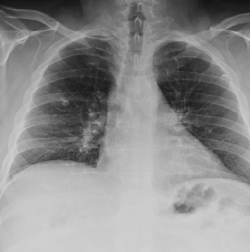

Vishesh Kumar, MD; Neeraj Saini, MD; Vivek Saini, MD

A 55-year-old female with history of triple negative breast cancer stage IIA status presents with pleuritic right-sided pain in the infrascapular region with progressive dyspnea on exertion over the past 2...